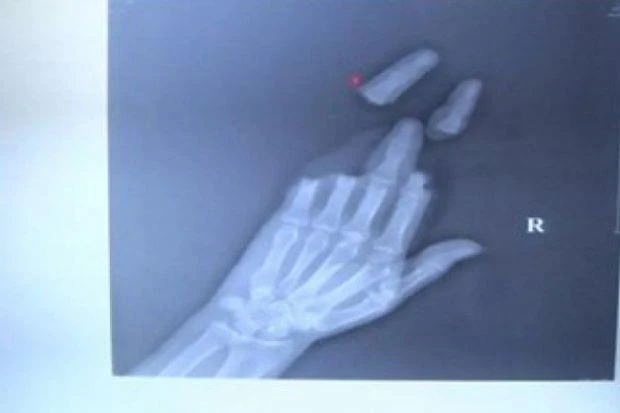

Ảnh chụp X-quang cho thấy ba ngón tay của một người đàn ông ở Giang Tô bị đứt rời sau khi thả diều trong gió lớn. Ảnh: SCMP.

Một người bị dây diều cắt lìa ba ngón tay, người còn lại thì lòng bàn tay bị cắt làm hai. Hai người đã cố kéo diều trở lại khi thấy trời chuyển giông. Cùng lúc đó, một cơn gió mạnh thổi tới, quấn dây diều quanh tay của họ.